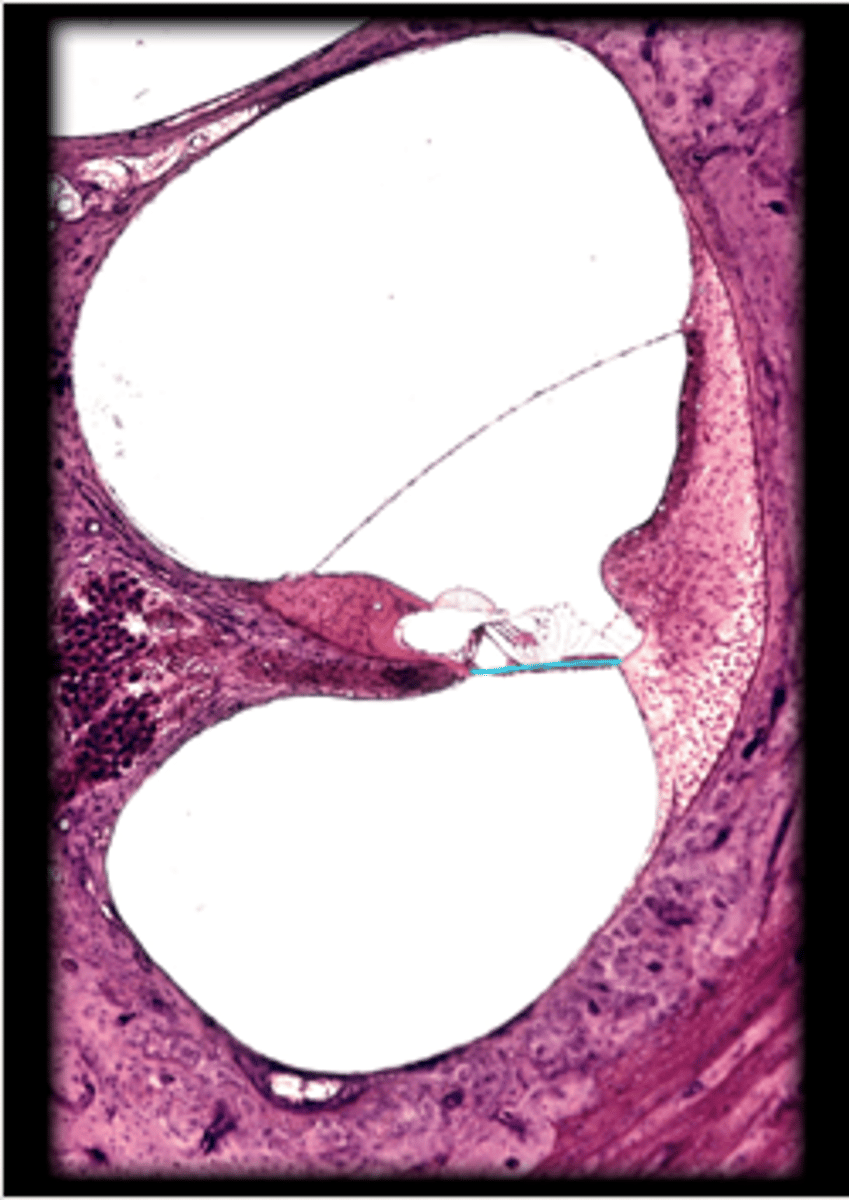

anterior chamber

posterior chamber

lens

suspensory ligament of eye

ciliary body

Iris